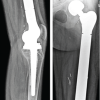

A 48-year-old male patient presented to the orthopedic clinic with swelling in the dorsum of the left hand since 5 years. The swelling was insidious in onset and gradually progressive. There was no history of trauma, constitutional symptoms, recent weight loss, or loss of appetite. No local rise of temperature or pain was noted in association with the lesion. On physical examination, a lobulated 5 × 4 cm sized swelling with well-defined margins was noted in the dorsum of the left hand (Fig. 1). The lesion spanned from the 3rd to 5th metacarpal region and had a smooth surface with soft to cystic consistency. The skin over the lesion was pinchable. The swelling was mobile in the horizontal direction, but not in the vertical direction. The swelling became prominent with the extension of fingers. On radiological examination of the left hand, there were soft tissue shadows seen in the dorsum, with a scalloping effect and cortical erosion noted in the distal end of the 3rd metacarpal bone (Fig. 2). Background mature skeleton was unremarkable. With clinical differentials of Ganglion cyst versus chondroid lesion, the patient was referred for a fine needle aspiration cytology (FNAC) procedure. FNAC showed abundant cellular material comprising of giant cells admixed with myxoid stromal elements in addition to the presence of multivacuolated cells, hence a report of “Giant cell rich soft tissue neoplasm” was rendered (Fig. 3). Since the margins of the tumor were well-demarcated, and FNAC exhibited a benign morphology, excision biopsy was performed and the specimen was sent to histopathological examination. Specimen post-formalin fixation revealed a 4.8 × 3.5 × 1.9 cm nodular solid mass with gelatinous to the myxoid surface (Fig. 4). Externally, the lesion was bosselated with lobulations noted on the cut surface. Solid areas were yellow to grey-tan in color with tiny cystic spaces embedded in it. Focal brown-black hemorrhagic areas possibly from the previous FNAC site were noted admixed with mucinous areas on gross evaluation. On microscopy, the sections studied showed a well-encapsulated neoplasm composed of lobules of tumor tissue separated by fibrous strands in a myxohyaline stroma (Fig. 5). The tumor cells were arranged in sheets, cords, and nests, were pleomorphic showing large epithelioid to ovoid shapes with vesicular to hyperchromatic nuclei and multivacuolated bubbly eosinophilic cytoplasm, resembling like physaliferous cells notably seen with chordoma (Fig. 6a-d). At places, the cell borders were indistinct and seem to be blending with the background myxohyaline matrix. No evidence of bony trabeculae or osteoid was noted in the lesion. There was intratumoral heterogeneity observed with solid, myxoid, microcystic, and hemorrhagic areas in varying proportions. With these findings on H&E staining, a primary provisional diagnosis of EAC was rendered on morphology with a note to perform IHC analysis for brachyury to consider EAC. In addition, a panel of IHC markers performed to rule out differential diagnoses, namely, soft tissue Myoepithelioma and other chondroid soft tissue lesions as well. The results of the IHC profile (Fig. 7 and 8) revealed that the neoplastic cells were positive for Pan-Cytokeratin (PCK) and Epithelial Membrane Antigen (EMA), S100, Ki-67 while negative for p63 and Glial Fibrillary Acidic Protein (GFAP) (Fig. 9a-d). There was a strong nuclear positivity for brachyury highlighting the neoplastic physaliferous cells (Fig. 10). Thus, a final diagnosis of Extra-axial soft tissue chordoma on the dorsum of the left hand was rendered. Post-operative as well as follow-up periods were uneventful as of now.